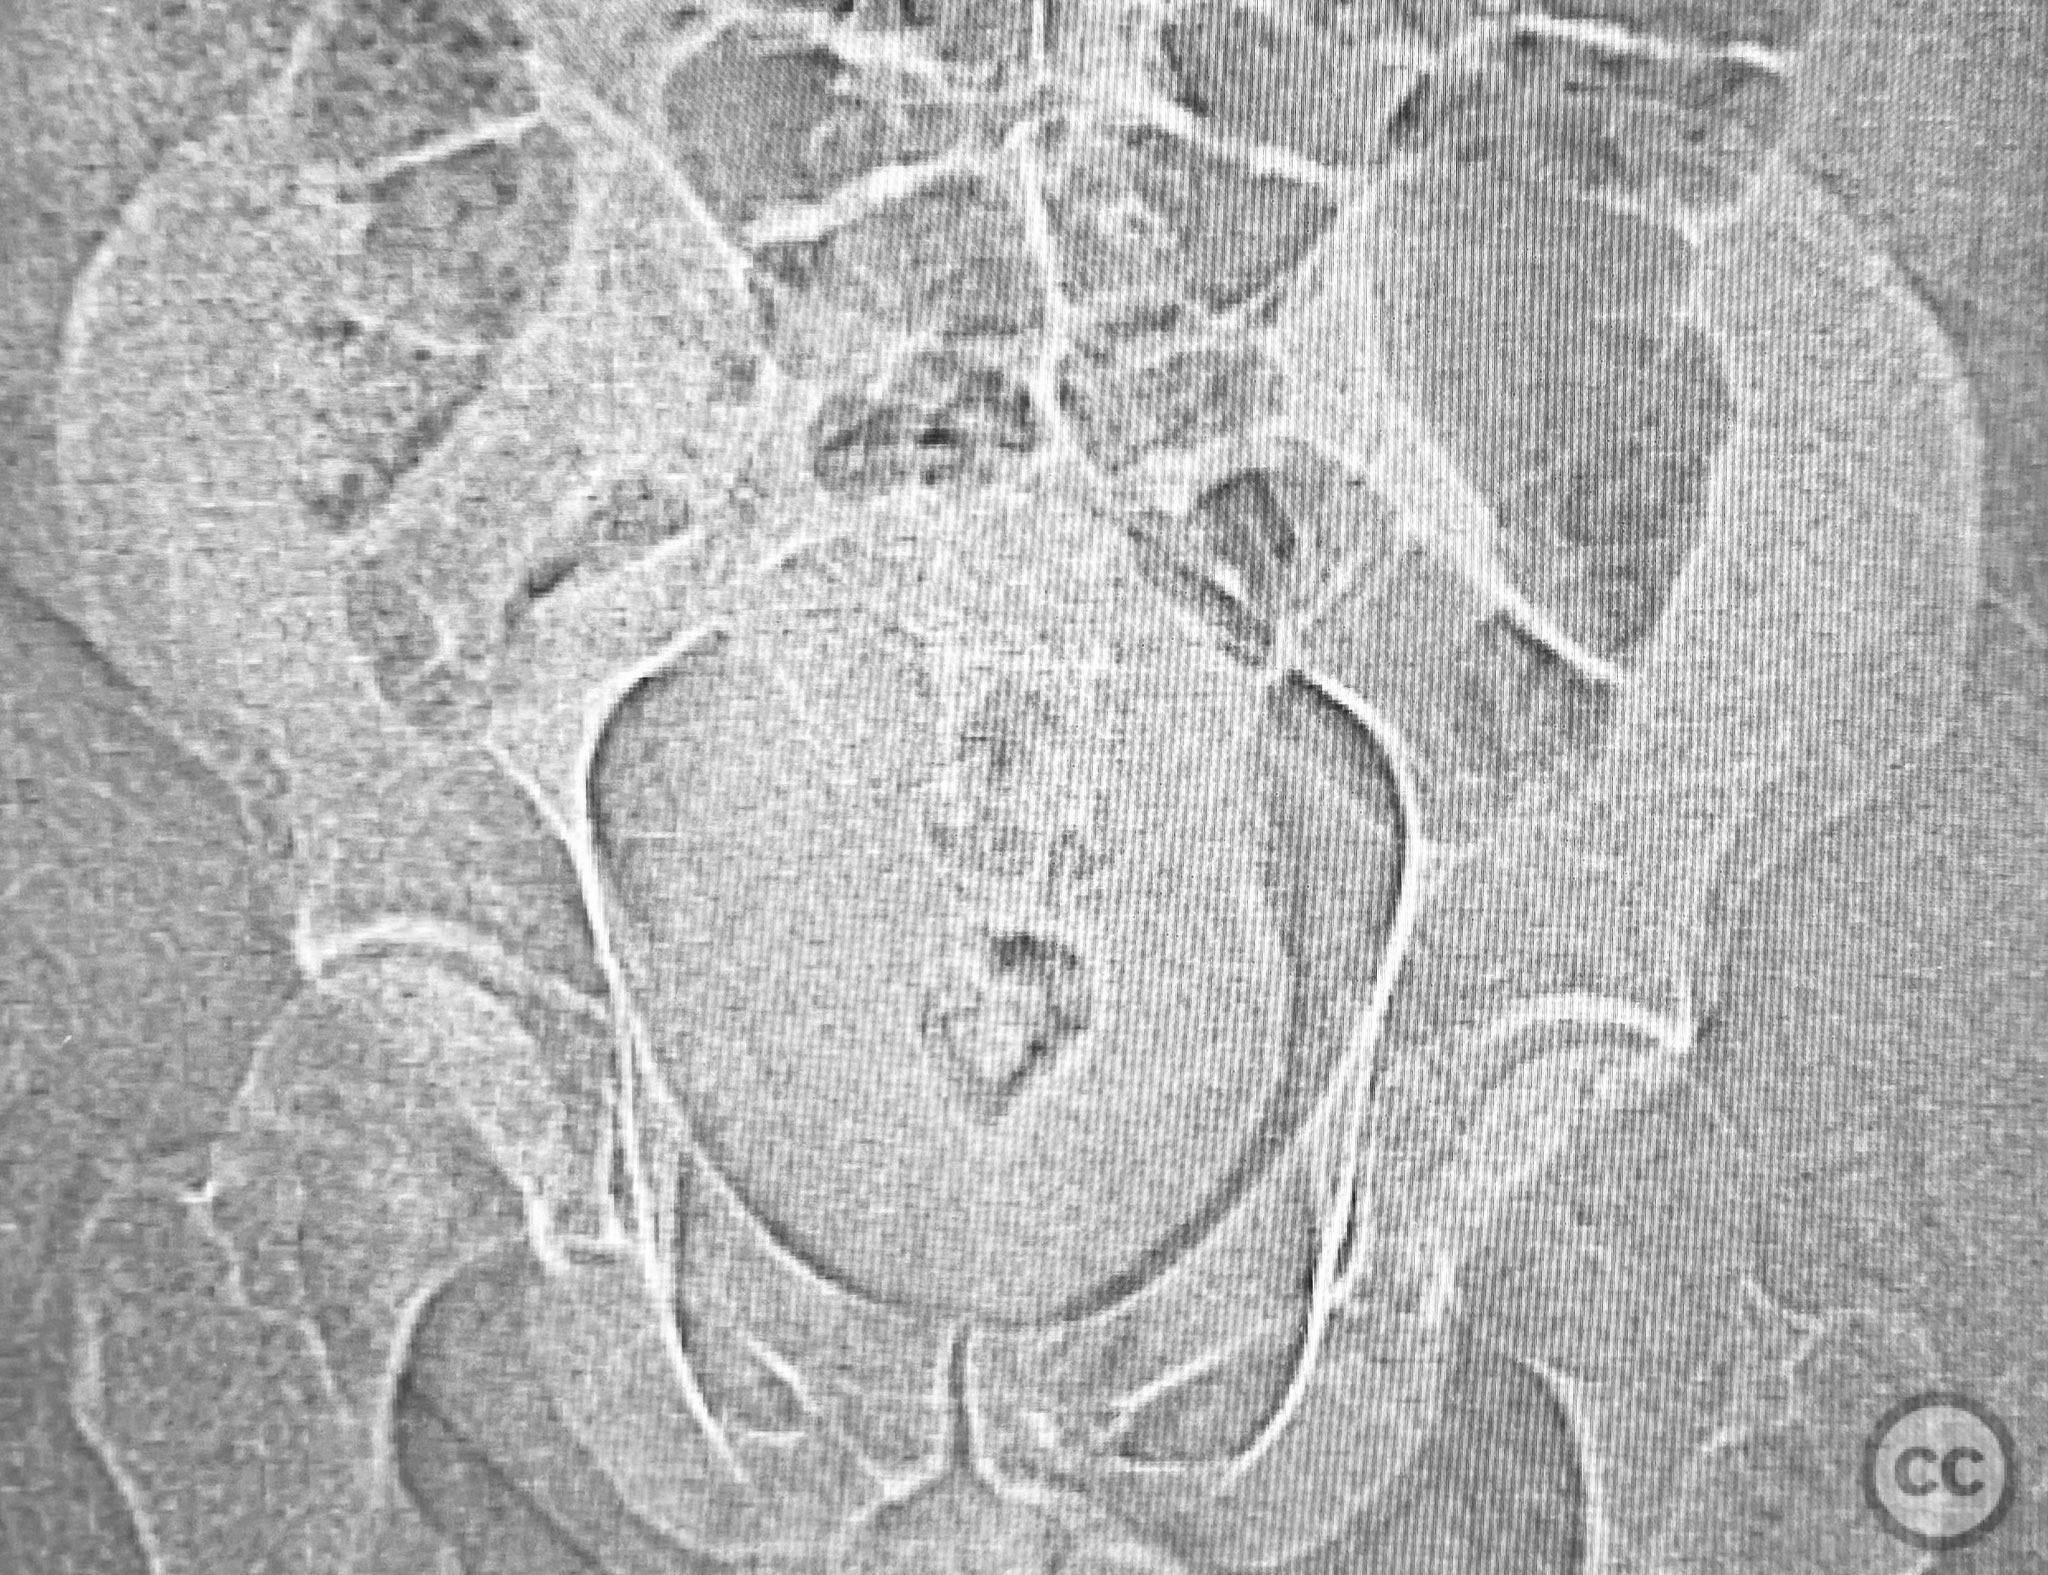

Clinical and radiological findings:  A patient involved in a motor vehicle collision presented with left hip pain exacerbated by any attempted movement. Initial axial and surface-rendered computed tomography (CT) imaging demonstrated an essentially nondisplaced posterior wall (PW) acetabular fracture (AO/OTA 62-A1.1). However, the anteroposterior (AP) scan image and coronal reconstructions revealed significant hip joint asymmetry. Examination under anesthesia with fluoroscopic guidance confirmed persistent joint incongruity, with the femoral head subluxating posteriorly at 50–60 degrees of flexion. A pure chondral fragment was identified as being interposed between the femoral head and the intact region of the posterior wall, accounting for the clinical and radiological asymmetry.